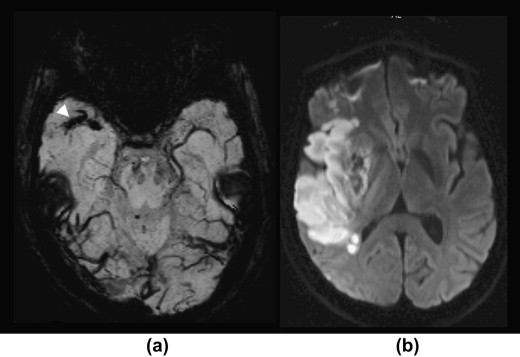

Stroke Syndrome:

Occlusion of branches to posterior temporal and occipital lobes from branches of the PCA